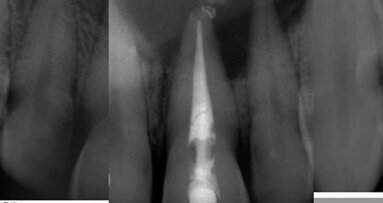

The patient was referred for root canal treatment (RCT) of tooth #36, the referring dentist having had difficulty in locating the root canal orifices. The ...

The patient reported on in this article was referred to my dental office by his general dental practitioner. There was a large cavity and symptoms of ...